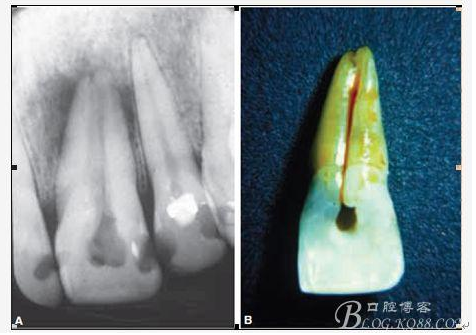

E、牙齒本身的畸形與缺陷 常見(jiàn)的比如下5的畸形中央尖以及切牙的舌側(cè)窩、深及根尖區(qū)的舌側(cè)溝或者牙中牙等等;